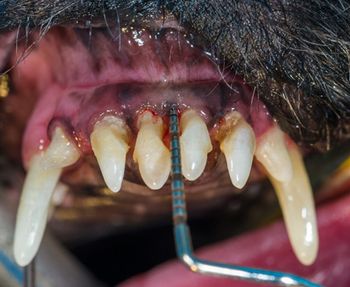

A buildup of calculus and plaque in this area can make a tooth prone to attachment loss, causing serious, painful disease if not caught early.